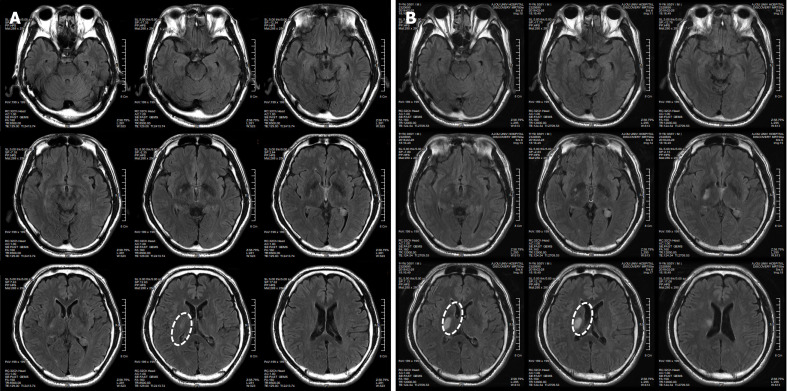

患者于2018年2月17日至18日出現(xiàn)暫時(shí)性無(wú)力癥狀,早上醒來(lái)后突發(fā)急性中風(fēng),導(dǎo)致左上肢和下肢癱瘓?;颊咴诖髮W(xué)醫(yī)院急診室被診斷為Rt紋狀體囊性梗死(圖1A)。他于2018年3月2日出院,僅接受了阿司匹林處方,因?yàn)楦鶕?jù)腦計(jì)算機(jī)斷層掃描 (CT) 掃描,他的腦血管正常,盡管他的病情在住院期間惡化(圖1)。出院當(dāng)天,他被送往康復(fù)??漆t(yī)院接受長(zhǎng)期康復(fù)治療。然后他于2018年3月13日來(lái)韓國(guó)首爾生物美容與健康公司 (bBHC)-干細(xì)胞治療與研究所 (STRI)接受干細(xì)胞治療。

圖1:微創(chuàng)人臍帶間充質(zhì)干細(xì)胞移植前患者的腦部計(jì)算機(jī)斷層掃描圖像。

患者在干細(xì)胞移植后約30個(gè)月拍攝腦部CT圖像以確認(rèn)病灶的大小。病灶縮小至0.6cm×0.3cm(圖4)。

圖4:微創(chuàng)人臍帶間充質(zhì)干細(xì)胞移植后患者的腦部計(jì)算機(jī)斷層掃描圖像。